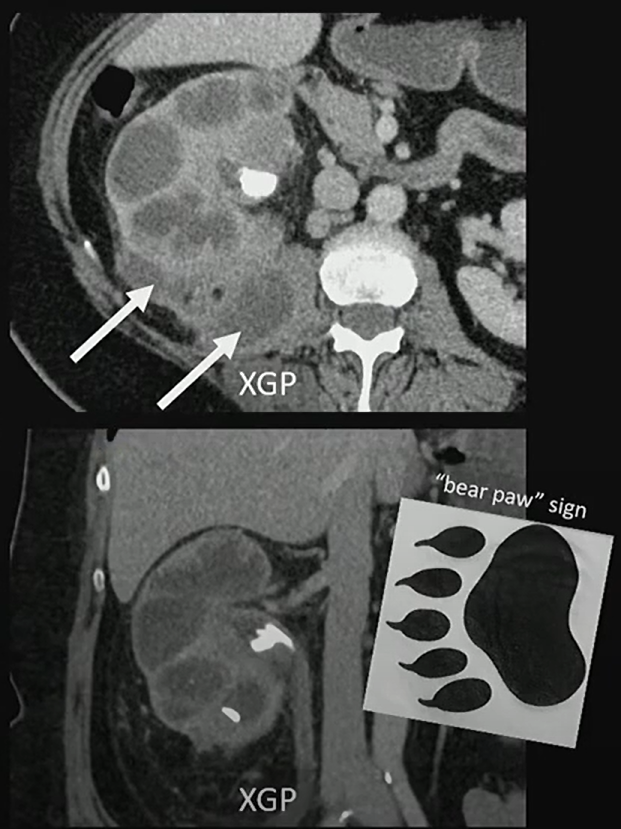

See staghorn calculi, perinephric inflammation, and an enlarged, poorly functioning kidney? Think xanthogranulomatous pyelonephritis! Read more